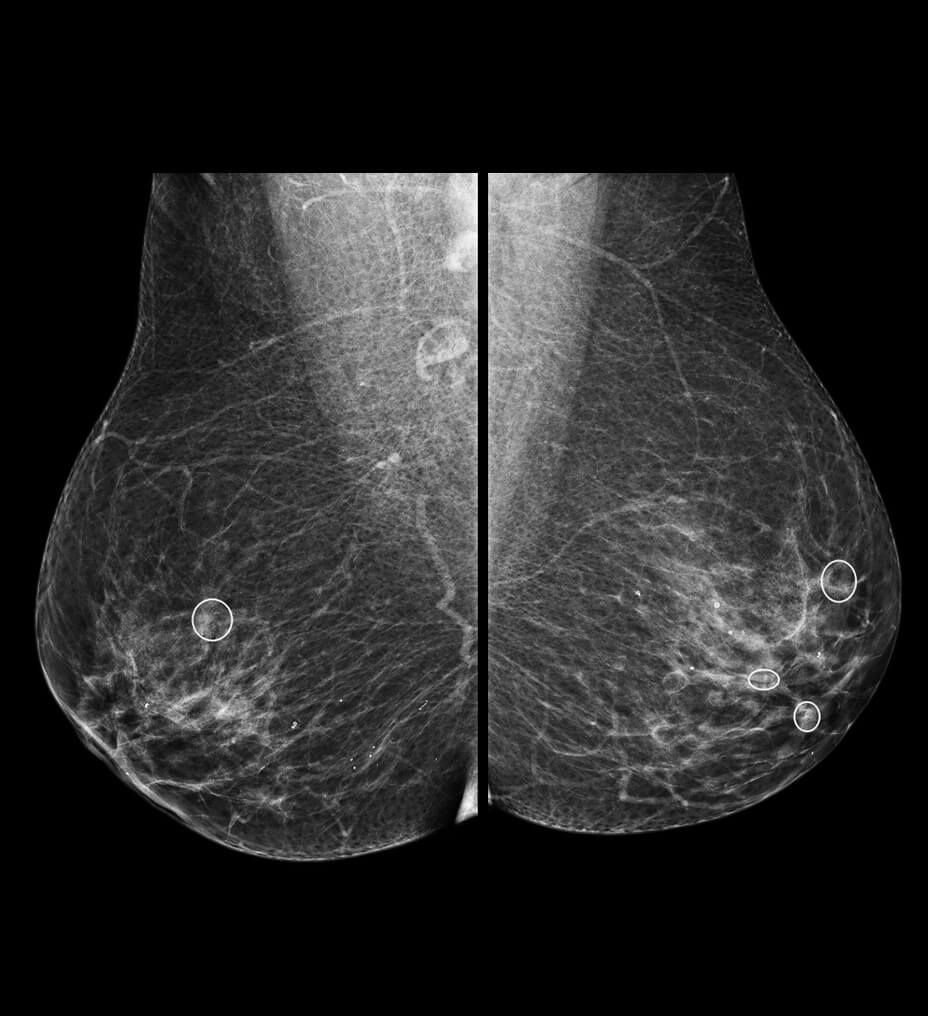

BREAST CANCER DETECTION

ProfoundAI for 2D

The SecondLook Computer-Aided Detection (CAD) system for mammography is intended to identify and mark regions of interest on screening and diagnostic mammograms from GE full-field digital mammography (FFDM) systems to bring them to the attention of the radiologist.